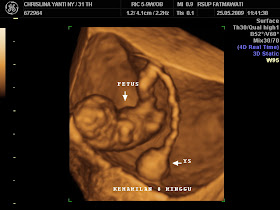

Gambar Janin 3 Bulan Usg 4 Dimensi